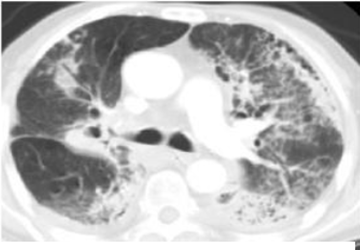

典型RILI影像表现及射野

WUj2fvhRjYOMcNYU.jpg EUuSa662a6s4XYS0.jpg

放射野内斑片影